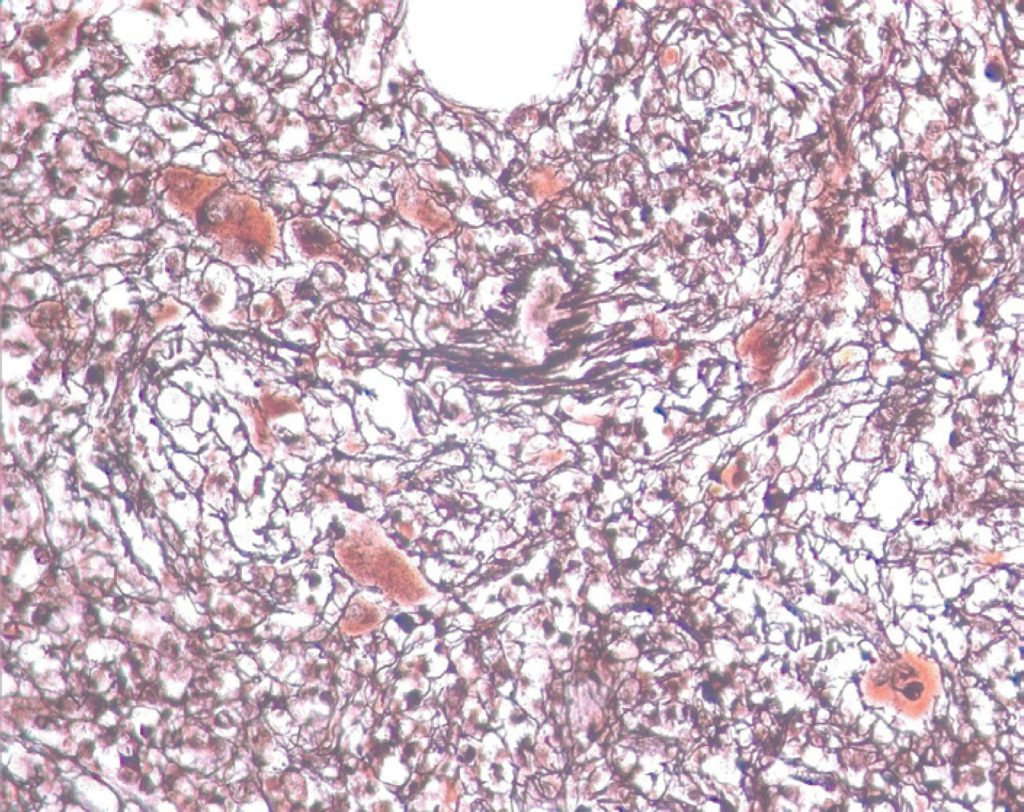

Mielofibrose acentuada, evidenciada por coloração específica (impregnação pela prata), mostrando megariócitos distorcidos de permeio a traves espessadas de reticulina

Mielofibrose acentuada, evidenciada por coloração específica (impregnação pela prata), mostrando megariócitos distorcidos de permeio a traves espessadas de reticulina